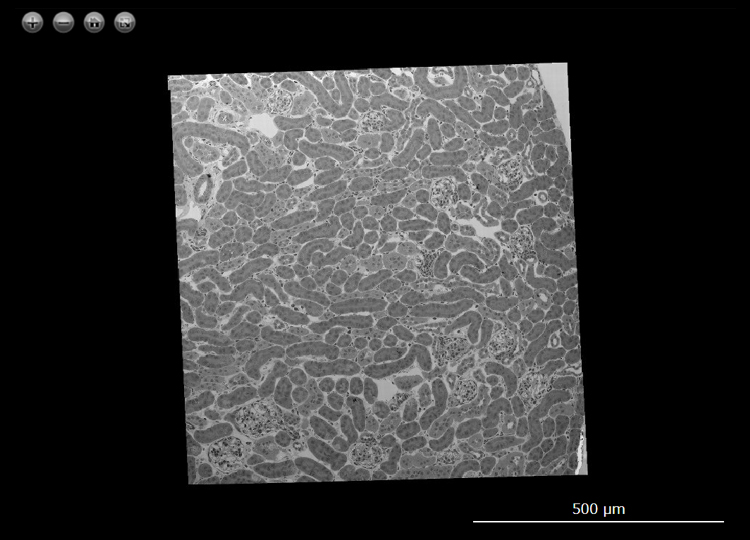

Ultrawide transmission electron microscopy image of a mouse kidney

The following data are ultrathin sections of a mouse kidney mounted on a SiN Window Chip imaged using the

Limitless Panorama (LLP) function, an automated montage system.

The images have been processed from wide-area images taken by LLP and can be viewed with a Web browser.

Sections mounted on a flat, grid-bar free SiN Window Chip allow us to view the entire area without any

wrinkles. To record this wide field of view in high resolution, automatic montage imaging (96 × 90 images)

was carried out using LLP at a pixel size of approximately 5.6 nm/pixel. The images thus obtained have

approximately 20 billion pixels, allowing us to observe the entire kidney cortex region (distribution of

glomeruli and the network of tubules) while maintaining a resolution that allows us to observe the basement

membrane structure of the glomerulus.

Sample : Mouse kidney

Imaging Device : JEM-1400 / Matataki Flash (2,048 x 2,048 pixels)

Image acquisition area : H 800 μm x W 760 μm with 8,640 (H 96 x W 90) images

Pixel size of the image : 5.6 nm/pixel

Total number of the pixels : 20 Gigapixel

Acceleration Voltage : 80 kV